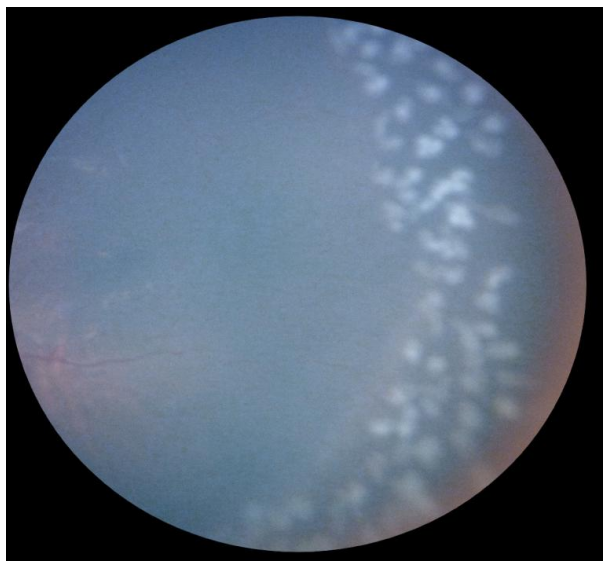

患儿的瞳孔仅有几毫米,眼内操作空间狭小如隙,视网膜薄如蝉翼,血管细若游丝,这对手术者的稳定性、精准度和耐力提出了极致的要求。荣军博在手术台前高度专注,手持激光探头,精准地在视网膜无血管的缺血区进行光凝,制造出数百个微小的、有序的灼烧点。最终,近千个精准的光凝点完美覆盖目标区域。手术持续到晚上7点多,顺利完成。

术后次日,通过眼底检查确认,视网膜病变得到了有效控制,新生血管活动性显著减退。眼科荣军博团队凭借精湛的技术和高效的协作,成功遏制了ROP病变的进一步恶化,为患儿保留了视力。患儿家属对医院的及时救治表示了深深的感激之情。